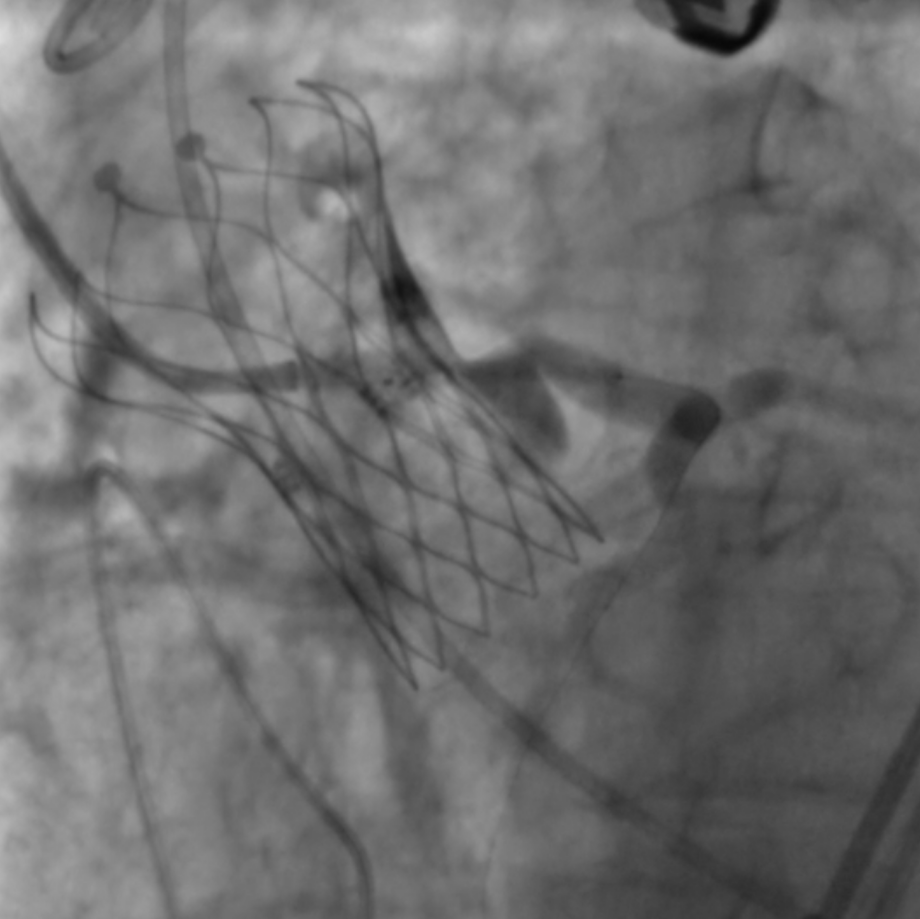

左冠植入4.0x19mm冠脉开窗支架

图片

5.0mm球囊后扩张支架近段

复查左冠开口面积恢复至12.76mm2